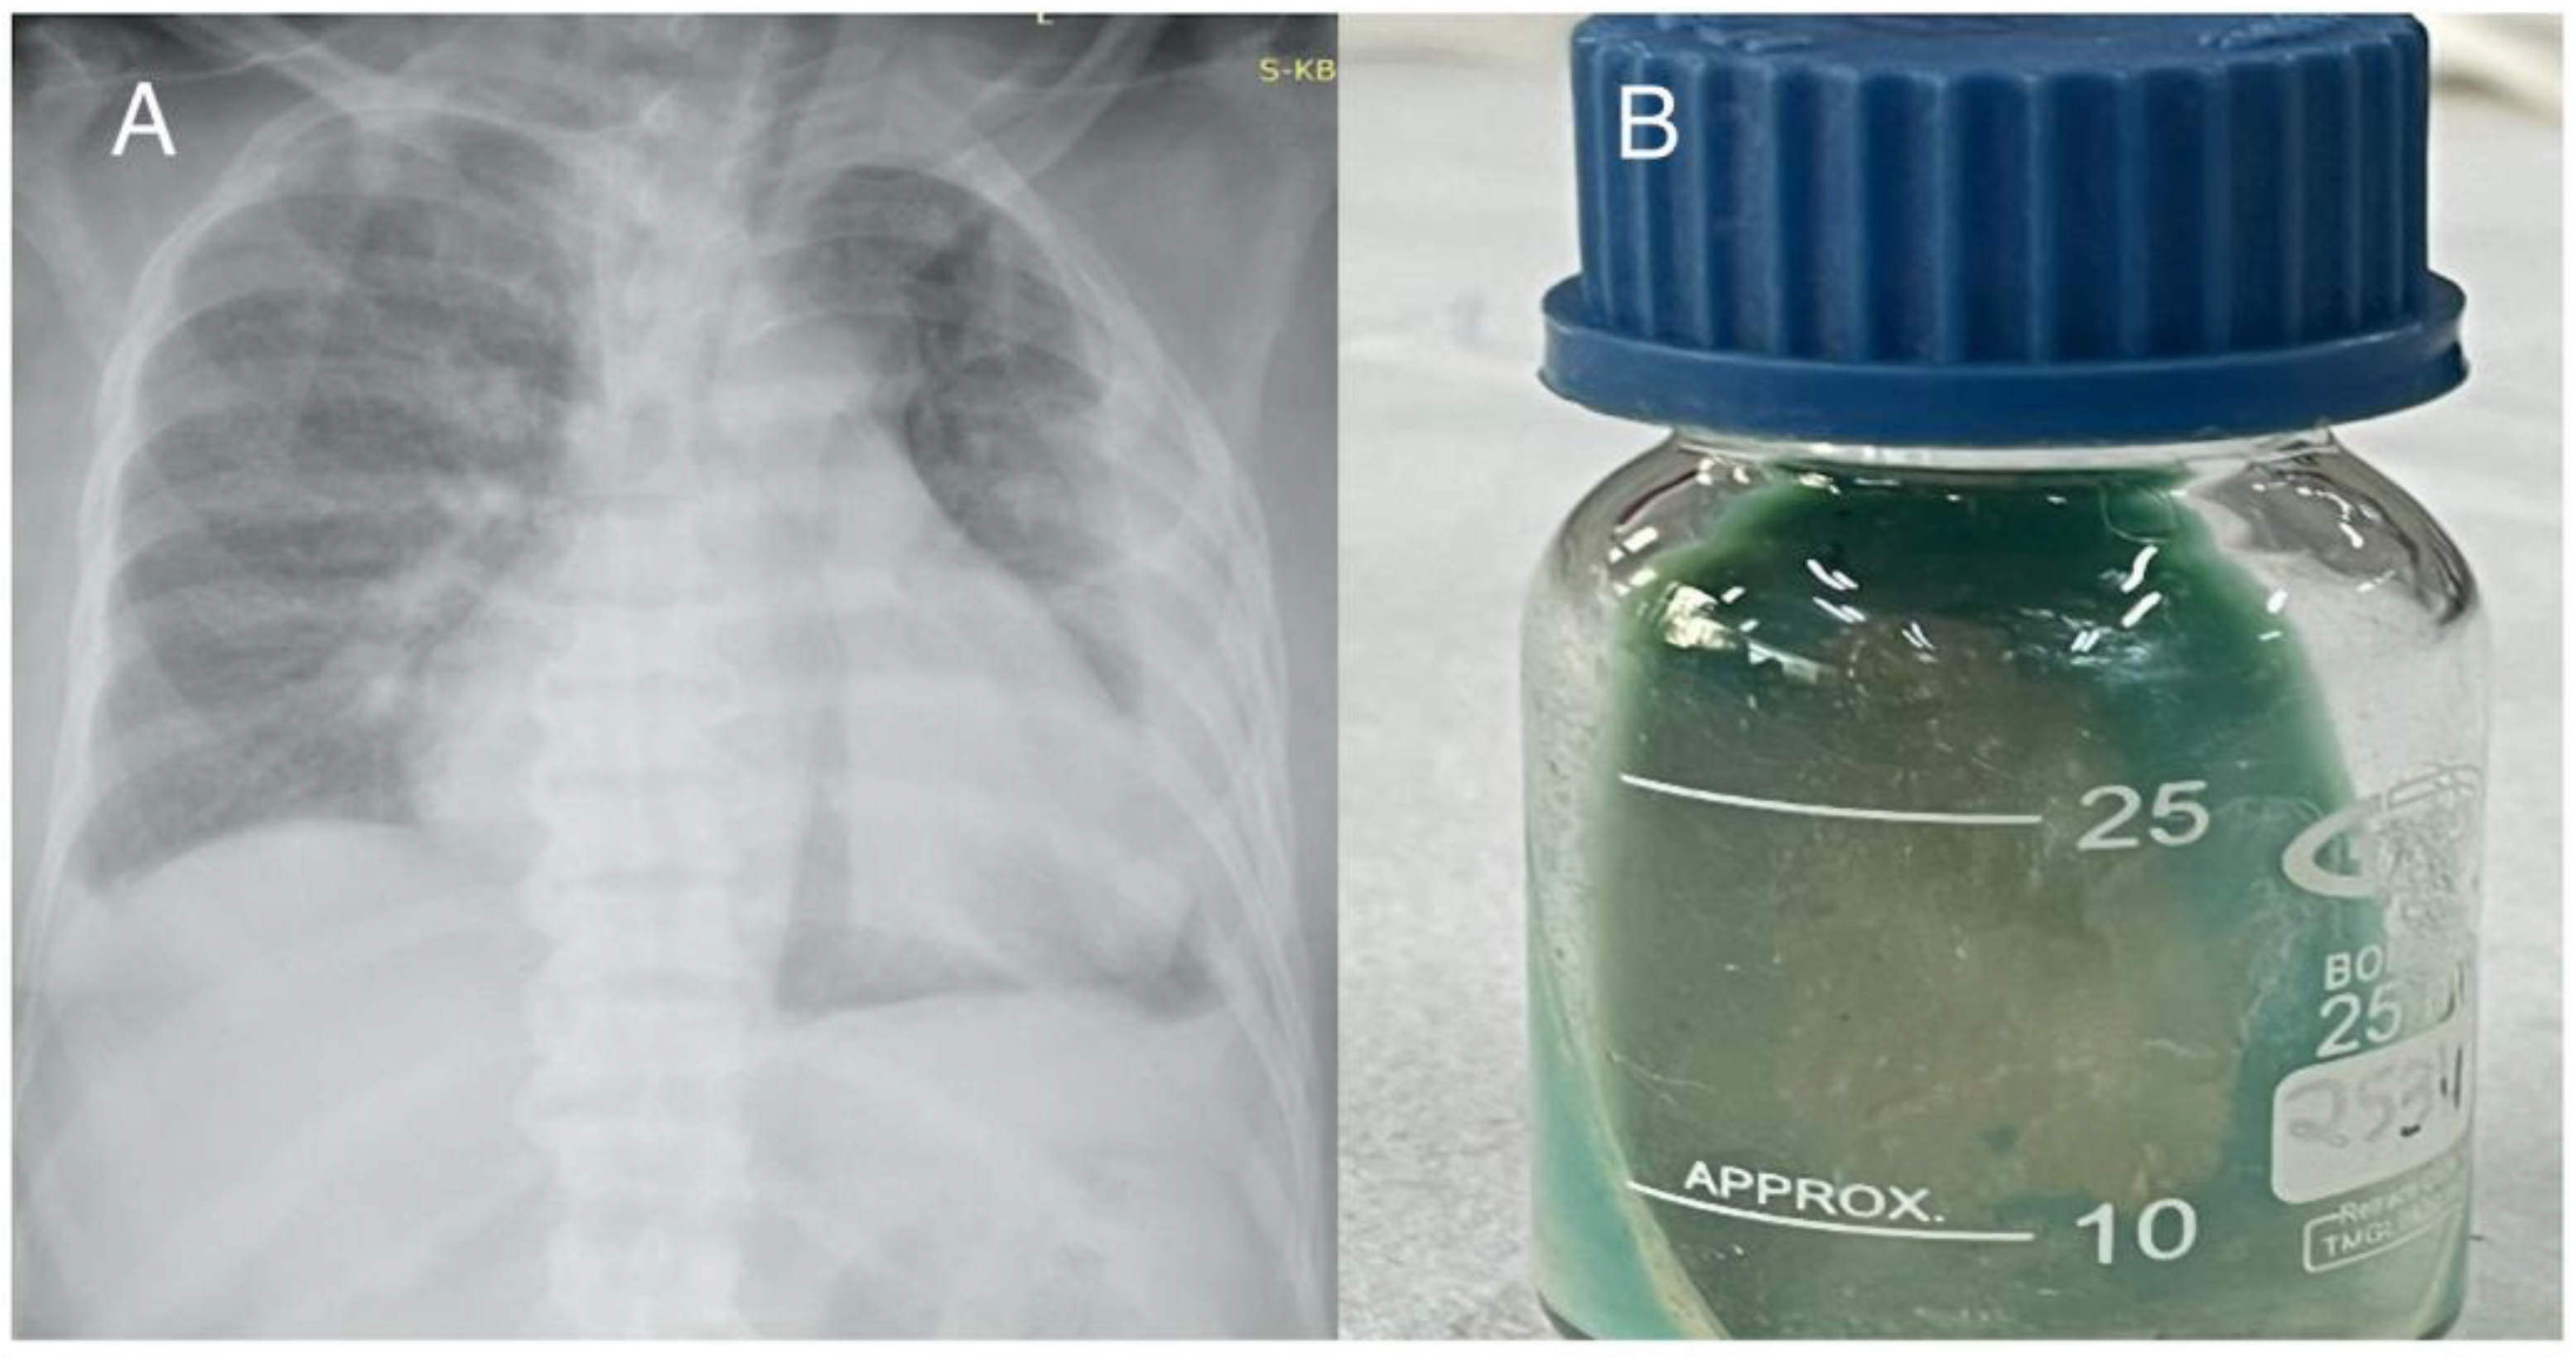

Case 3